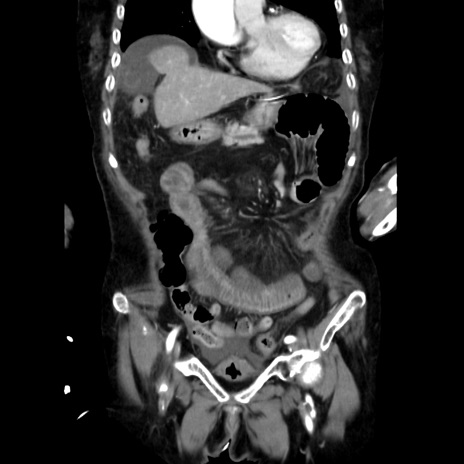

症例40(冠状断像)

【症例】90歳代女性

【主訴】腹痛・嘔吐

【現病歴】 食欲低下、嘔吐があり昨日他院受診。肺炎と診断され入院となる。入院後より腹部全体に圧痛あり。胃管留置され経過みていたが、症状持続するため、

当院転院となる。

【既往歴】胸椎圧迫骨折、胆石症

【身体所見】腹部:中央に激痛あり、圧痛あり、反跳痛不明

【データ】WBC 17100、CRP 18.82

冠状断像